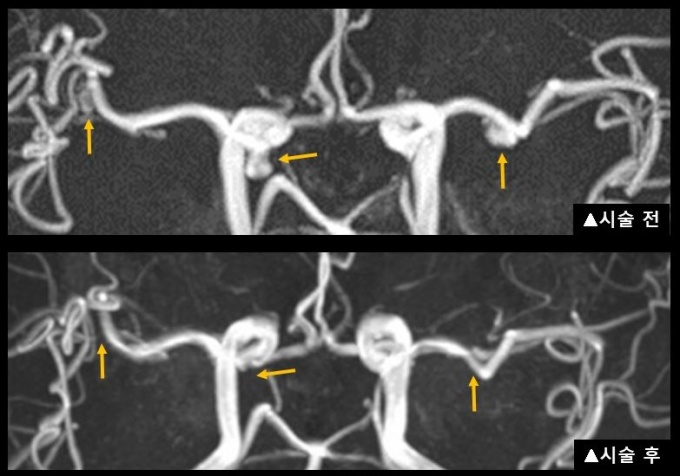

스텐트까지 삽입해 입구를 막은 후 시술해야 하는 상황이었지만, 서 교수팀은 가급적 스텐트를 사용하지 않기 위해 두 개의 미세 카테터로 시술했다. 하나의 카테터로는 코일이 빠져나오지 않도록 뇌동맥류 입구를 지지하고, 나머지 하나로는 코일을 삽입했다.

특히 환자가 고혈압까지 앓고 있어 혈관 변형이 매우 심하고 탄력이 떨어져 코일을 정확하게 넣기 어려웠지만, 3차원 뇌혈관 조영술을 시행해 환자 상태에 맞게 미세 카테터 길이와 방향을 변형시켜 성공적으로 코일을 삽입했다.

서 교수팀은 황 모씨의 4개 뇌동맥류 중 3개를 치료하고, 나머지 한 개는 크기가 작고 파열 위험이 낮아 치료하지 않고 경과를 지켜보기로 했다. 황 씨는 부작용 없이 바로 일상생활이 가능할 정도로 회복해 다음 날 퇴원했다.